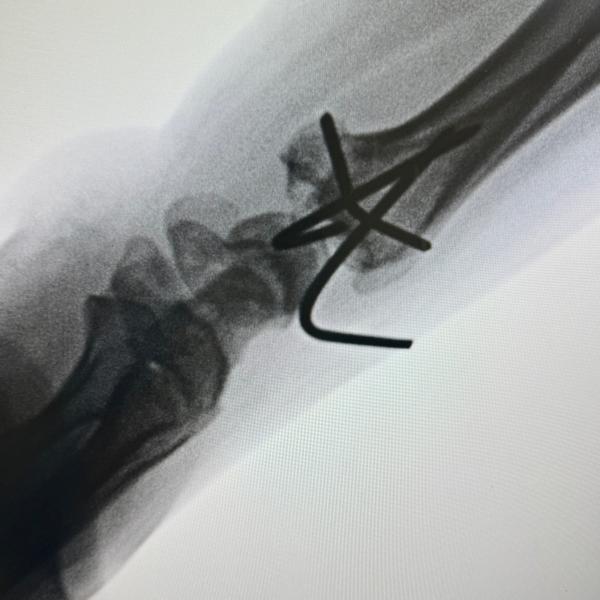

Distal end radius fracture of young patient operated with. Closed reduction and K wire fixation

Distal end radius fracture of young patient operated with Closed reduction and K wire fixation